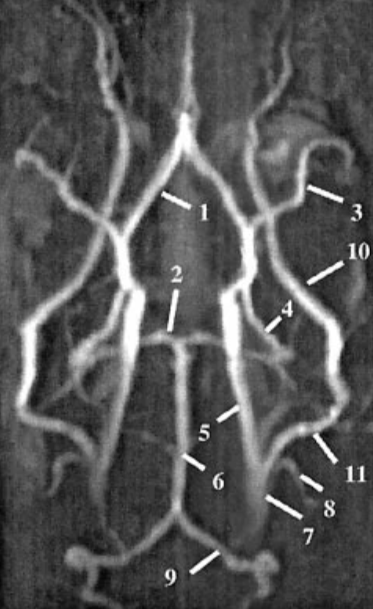

Please label the reconstructed MR angiogram

Please label this coronal CT scan